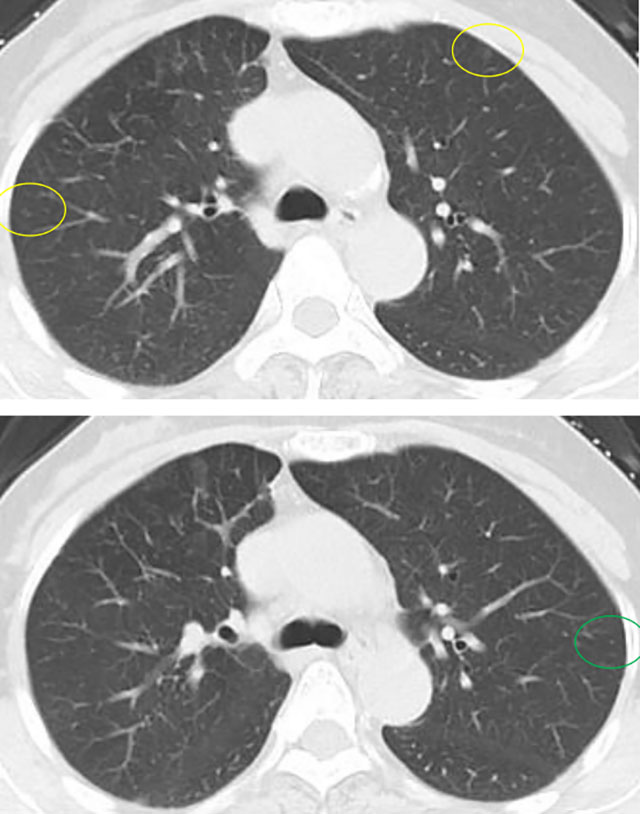

几年前影像展示与分析,5mm层厚、无薄层。

上图中红色圈原位癌可能性较大,尤其右肺上叶尖段二个结节,可见血管增粗及血管弯5mm层厚,无薄层重建;橙色圈多考虑不典型增生可能性大;黄色圈大概只是肺泡上皮增生;绿色圈考虑是良性的。